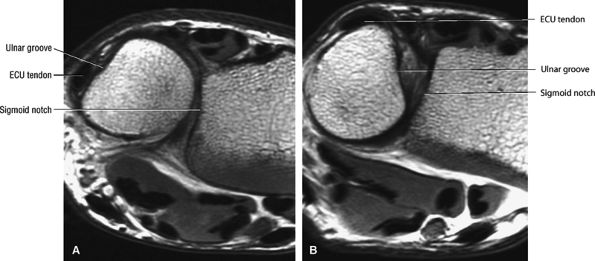

-

In a neutral position the ulnar styloid is located medially.

In pronation the ulnar styloid points volarly.

In supination the ulnar styloid points dorsally.

The dorsal radioulnar ligament and palmar radioulnar ligament are the primary ligamentous stabilizers of the distal radioulnar joint and on axial plane images are seen coursing on both the dorsal and volar sides of the TFC, at the level of the base of the ulnar styloid, where the ligaments insert. Tears of the dorsal radioulnar ligament are associated with volar subluxation of the ulna. Tears of the volar radioulnar ligament are associated with dorsal subluxation of the ulna. Distal radioulnar joint instability is suggested when the ulnar head is abnormally subluxed or dislocated with respect to the radius, beyond the normal range of motion allowed for pronation and supination. In addition to ligamentous injury, osseous injuries such as fractures at the base of the ulnar styloid also may lead to distal radioulnar joint instability.